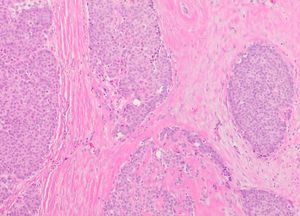

유두상 관내 상피내 암종(PDCIS)의 저배율 현미경 사진

전형적인 유두상 관내 상피내 암종(PDCIS) 병변의 현미경적 조직병리학적 특징은 헤마톡실린 및 에오신 염색을 통해 관찰할 수 있다. 병변은 유두 모양의 잎(가늘고 손가락 또는 잎사귀 모양의 구조)이 섬유혈관성 중심(core)을 가지며, 이 잎들이 하나 또는 여러 층의 신생물성 상피세포로 덮여 있는 형태로 나타난다. 상피 세포는 주로 키가 크고 폭이 좁은 원주 모양이며, 세포 핵은 관 부착 부위 가까이에 위치한다.[4] 잎의 표면을 덮는 상피 세포는 일반적으로 고형(solid), 사상(cribriform, 즉 크고 다양한 크기의 둥근 공간으로 관통된 많은 세포 둥지 형태), 또는 미세유두상(micropapillary) 패턴을 보인다.

때로는 일반적인 신생물성 상피 세포 외에, 풍부하고 투명한 세포질을 가진 '구형 세포'(apocrine cell)라는 두 번째 세포 집단이 관찰될 수 있다.[7] 이 세포들은 에오신 염색 시 분홍색 또는 붉은색으로 염색되는 호산성 세포질을 가진다.[6] 이러한 구형 세포가 동반된 PDCIS는 '아포크린 변이형'(apocrine variant)으로 분류되기도 한다.[3]

근상피세포는 일반적으로 유두상 잎의 주변부에는 존재하지만, 병변이 발생한 관 내부에서는 발견되지 않는다.[4][7] 섬유성 피막이 있거나 주변에 근상피세포가 없는 것은 종양이 PDCIS가 아닌 피막 유두상 암종(EPC) 또는 고형 유두상 암종(SPC)임을 시사하는 강력한 지표이다.[3] PDCIS 조직 내에는 죽은 세포들이 쌓여 형성된 "코메도형 괴사" 부위가 관찰될 수도 있다.[6]

면역조직화학 연구 결과, PDCIS 종양 세포는 상당수에서 에스트로겐 수용체(ER)와 프로게스테론 수용체(PR)를 발현하는 경향이 있다. 2009년 54명의 PDCIS 환자를 대상으로 한 연구에서는 각각 34명(63%), 31명(57%)의 종양 세포에서 ER, PR 발현이 확인되었고, 35명(65%)에서는 HER2/neu 단백질 발현이 나타났다.[14] 최근 보고에 따르면 대부분의 PDCIS 종양 세포는 에스트로겐 수용체를 강하게 발현하며,[6] 에스트로겐 수용체를 발현하지 않는 경우는 일반적으로 조직학적으로 더 나쁜 예후를 시사하는 특징을 보인다.[13]

현재까지 PDCIS 종양 세포에서 반복적으로 나타나는 특정 유전자 변형은 확인되지 않았다.[6] 간혹 발견되는 유전자 변형은 저등급 관내 상피내 암종(low-grade DCIS)에서 관찰되는 것과 유사한 양상을 보인다.[4]